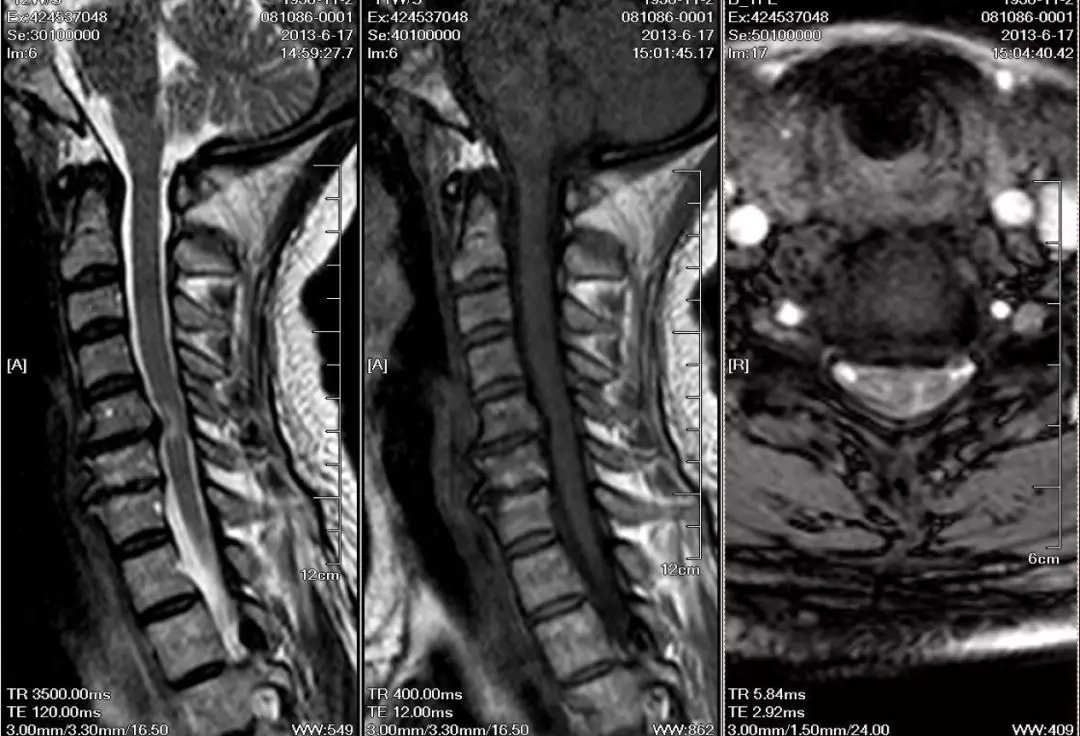

这是一个由于椎体后缘的骨刺导致的脊髓型颈椎病,我们可以看到脊髓受压,脊髓有水肿变性,T1加强可以看到明显的骨刺,对于脊髓型的颈椎病,预后如果属于椎间盘突出和脱出,软性致压物,手术以后效果比较好。如果是椎管有狭窄,骨刺,后纵韧带的骨化压迫,这种发展比较慢,治疗预后也比较差,如果有明显脊髓变性的,预后则更差。